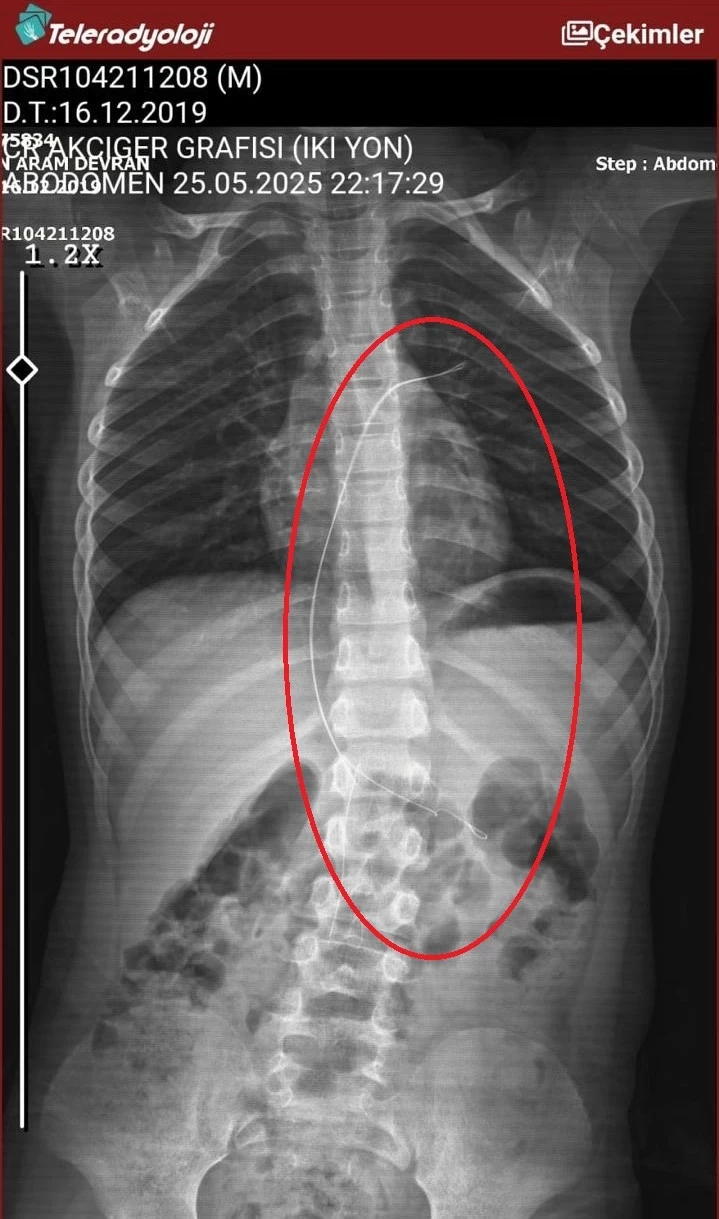

Çekilen röntgende Ötün’ün vücudunda 18 santimetrelik kateter olduğu görüntülendi. Ötün’ün 3 yıl önce Stevens- Johnson sendromu nedeniyle tedavi gördüğü sırada damar yoluna takıldığı ve çıkarılmadığı ortaya çıktı.

Ötün 5,5 saat süren riskli bir ameliyata alınarak 18 santimetre uzunluğundaki kateter çıkarıldı. Ameliyat sonrası yapılan incelemelerde kateterin kalp kapakçığına ve ciğerlerine zarar verdiği öğrenildi.